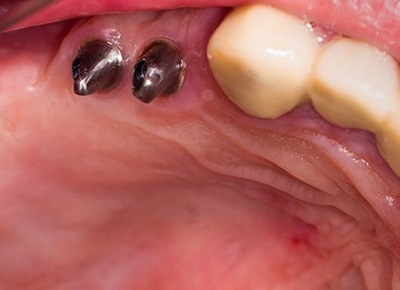

치아 중 어금니는 음식물을 섭취할 때 잘게 부수어 소화가 잘 되도록 돕는 치아입니다. 그러나 음식물을 섭취할 때 음식물 찌꺼기가 남거나 칫솔이 잘 닿지 않는 부위로 충치 발생이 잦은 부위이기도 한데요. 어금니는 충치가 생기기 쉬운 치아로 손실 및 상실로 인한 임플란트 관리를 많이 하는 부위이기도 합니다.

치주질병이나 잇몸 염이 자주 발생할 수 있어 잇몸 관리와 병행하는 사례도 많은 편이죠. 이처럼 어금니가 소실되면 정상적인 저작 기능이 힘들어 식사하는데 매우 큰 불편함을 느낄 수 있습니다. 이 경우 임플란트를 통해 자연 치아에 가까운 씹는 힘과 형태를 되찾을 수 있으며 저작 능력이 강조되는 어금니를 대체하는데 있어 어금니임플란트는 가장 효율적인 관리라고 볼 수 있습니다.